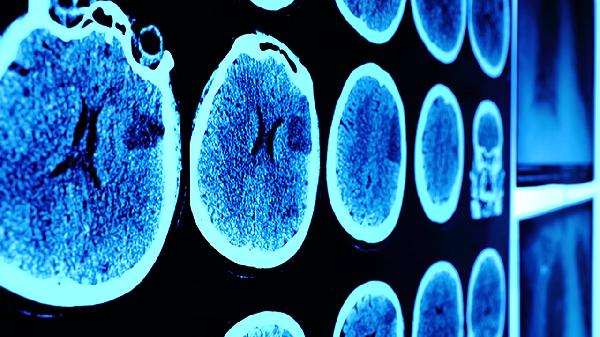

脑震荡后应保持适度休息但避免长期卧床,逐步恢复轻度活动如散步有助于改善症状。饮食注意补充富含欧米伽3脂肪酸的深海鱼、坚果等食物,限制咖啡因摄入。若症状持续超过3个月或出现视力模糊、频繁呕吐等加重表现,需及时复查头颅CT或MRI排除器质性病变。康复期间避免剧烈运动或可能造成头部二次受伤的活动,心理疏导对缓解焦虑情绪尤为重要。